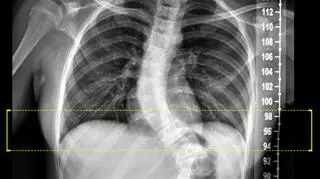

Zdjęcia rentgenowskie kręgosłupa 13-latki

13-letnia Natalia jeszcze kilka dni temu miała kręgosłup ze skrzywieniem, które wynosiło 80 stopni. To rzadka wada. Dzięki lekarzom ze Szczecina po skoliozie prawie nie ma śladu. - Zaczynam nowy rozdział w moim życiu - mówi dziewczynka.

Pręty zamówiono na miarę we Francji. Jak dowiedziała się reporterka TVN24, dobrano je na podstawie zdjęć rentgenowskich. Pod uwagę trzeba było wziąć długość odcinka kręgosłupa oraz kąt skrzywienia, a to w przypadku 13-latki wynosiło ponad 80 stopni.

Zdjęcie przed operacją